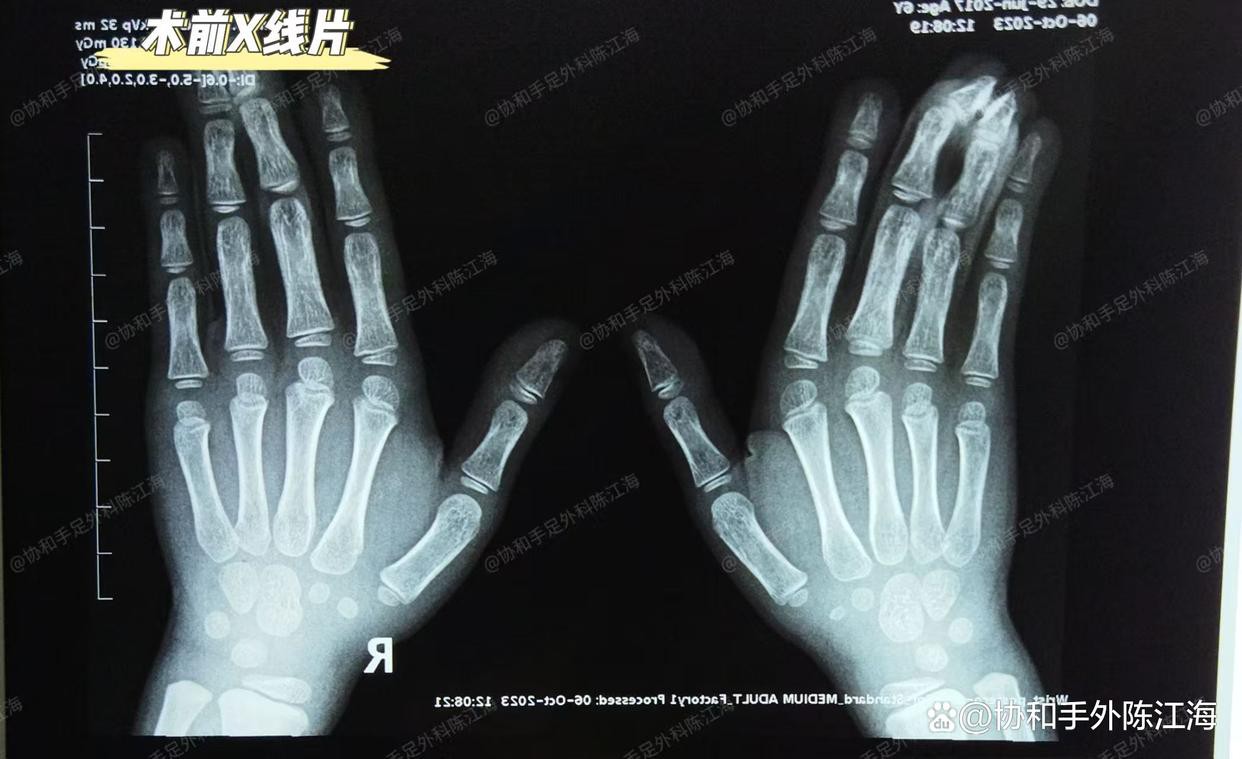

Leikkausta edeltävä röntgenkuva